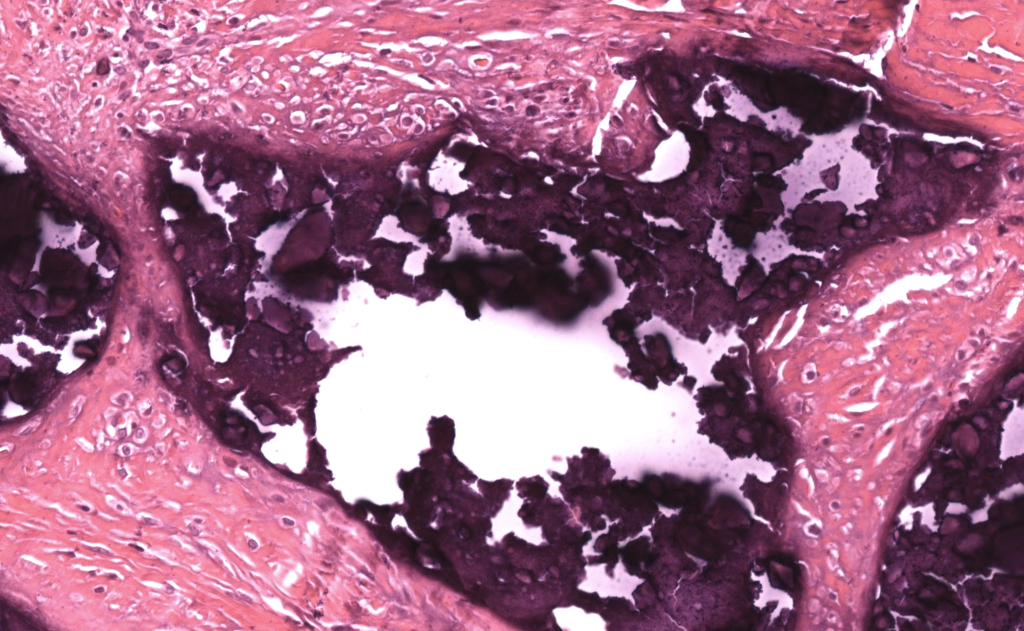

- Patrón básico

- Dermatitis de depósito: material basófilo amorfo/granular en dermis y/o panículo, con reacción granulomatosa a cuerpo extraño alrededor. Reiter 2011, Touart 1998

- Hallazgos en H&E

- Depósitos basófilos nodulares o laminares en dermis reticular y/o tejido celular subcutáneo.

- Células gigantes multinucleadas e histiocitos rodeando el depósito, con fibrosis variable.

- Epidermis normal o adelgazada; ulceración cuando la lesión drena. Reiter 2011, Jiménez-Gallo 2015

- Calcifilaxis: calcificación de la media vascular, trombosis luminal y necrosis isquémica de dermis y panículo. Jiménez-Gallo 2015

- Tinciones especiales / IF / IHQ

- Von Kossa (depósitos negros) y alizarina roja S (rojo-anaranjado) confirman calcio cuando los depósitos son sutiles. Touart 1998